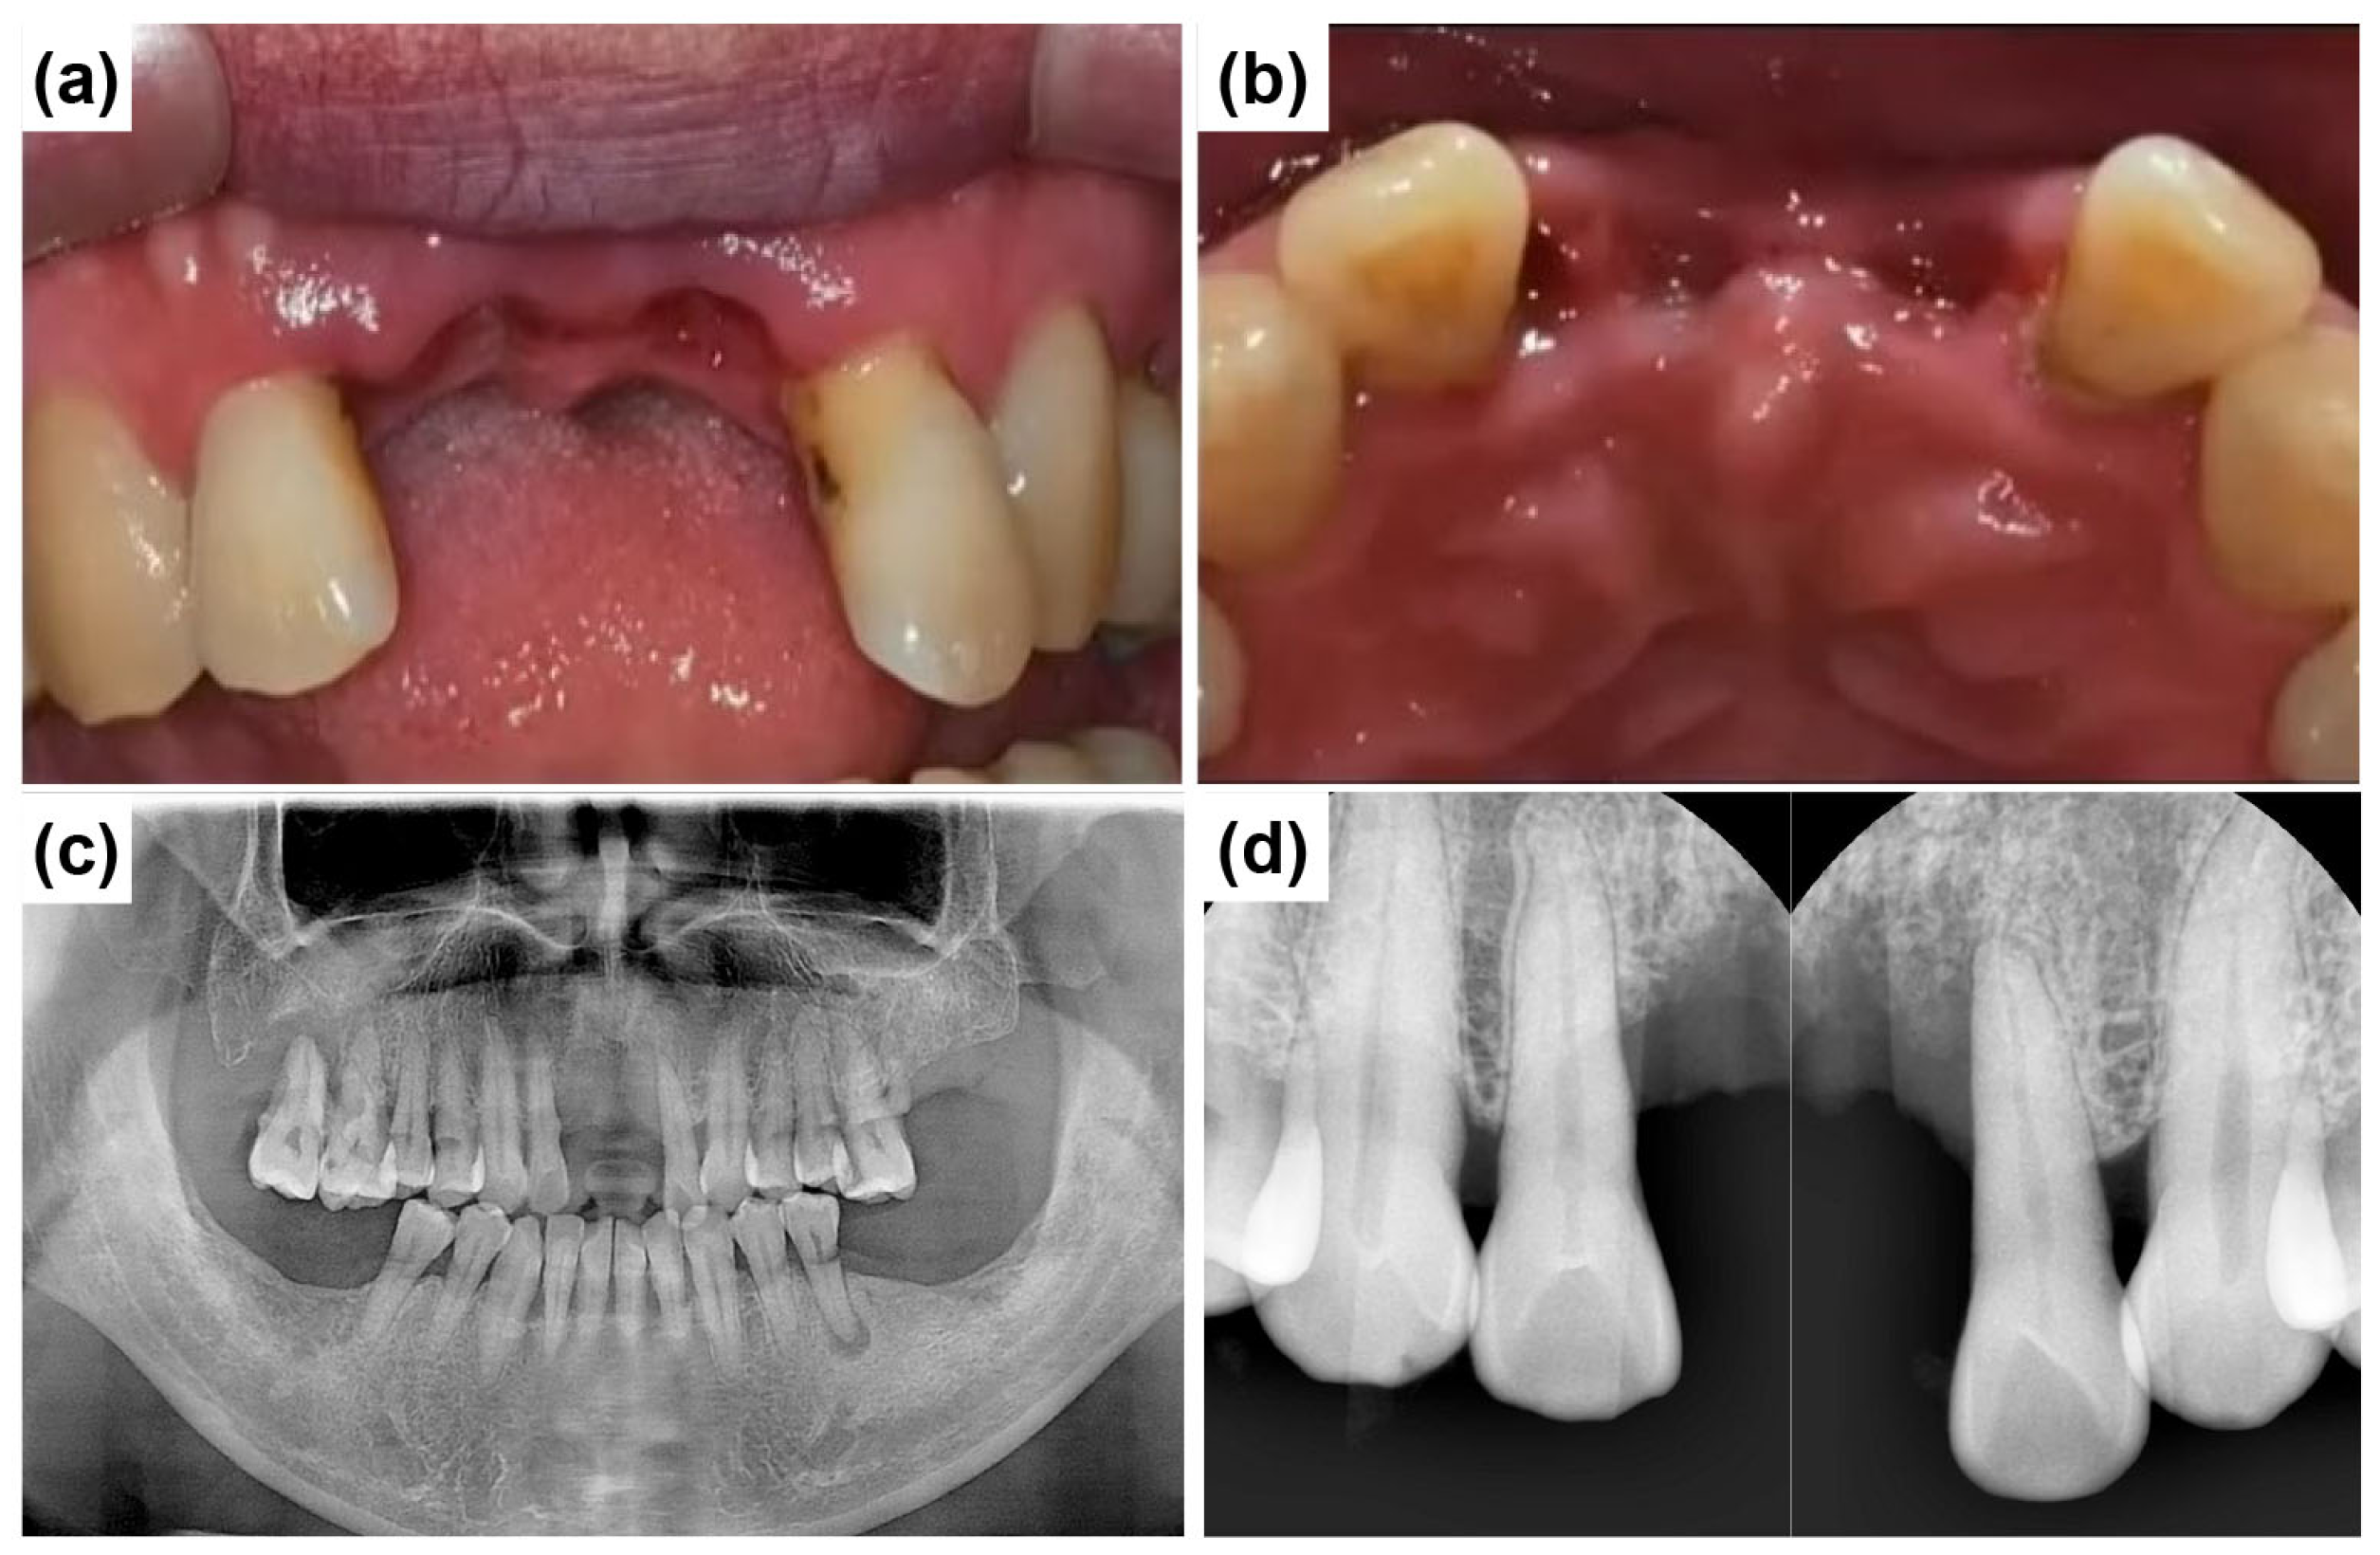

A 50-year-old male patient reported to the Mir Dental Hospital at Daegu without tooth #11. The patient stated that tooth #11 was lost to periodontal disease approximately five months before his visit. He was a non-smoker and had no significant systemic conditions. Intraoral examination confirmed the extraction site of tooth #11 (Figure 12a). Clinical inspection revealed severe alveolar bone loss around the apex of the missing tooth #11. The patient expressed concerns regarding the color and morphology of teeth #21 and #22, requesting esthetic improvements. Consequently, the treatment plan was expanded to include new prosthetic restorations for teeth #21 and #22 (Figure 12b). Figure 12c shows the initial panoramic radiograph, illustrating the patient’s overall periodontal condition and alveolar bone status.

Figure 12.

Preoperative clinical and radiographic evaluation. (a) Missing tooth #11 at the initial visit. (b) Preparation of teeth #21 and #22 for fabricating the new restoration. (c) Initial panoramic radiograph shows overall periodontal condition and alveolar bone status.